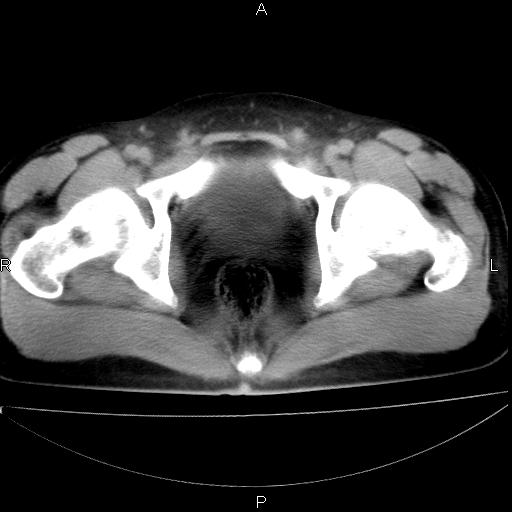

男 25岁 自述 尿频尿急,排尿困难20多天.无腰痛, b超说左肾盂轻度积水,左输尿管上端扩张.未见结石影. ct我看双侧肾盂轻度积水,双输尿管上端都扩张,大家看看能看见结石吗?

双肾轻度积水,双侧输尿管上段扩张(原因待查)。

双输尿管扩张下端未见高密度结石和输尿管晕轮征,不好说是结石.增强后如何?

双肾轻度积水,未见明确结石,薄层对结石检出率较高。

双肾盂及双输尿上段轻度积水,双输尿管未见明显结石影。